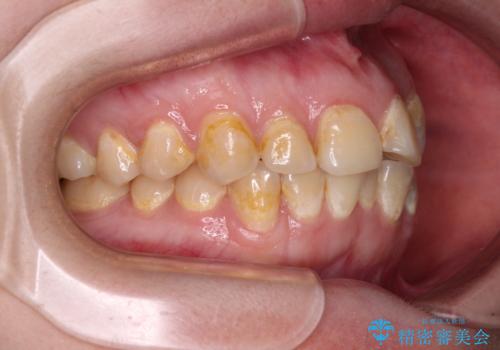

- 前歯のデコボコとクロスバイトが気になり、インビザラインによる矯正治療を希望して来院された患者様です。

上顎側切歯(上の真ん中から2番目の歯)が舌側転位している場合、無理して動かそうとすると歯髄壊死を起こすリスクが高い印象があります。

インビザライン単体でも治療は可能ですが、安全策としてインビザラインで歯列を移動する前に上顎前歯をワイヤー矯正で整え、その後上下歯列をインビザラインにて矯正治療を行うこととしました。

舌側転位している側切歯特有の、切縁の位置が不揃いであったり、根元が内側に引っ込んだ状態であったりという、インビザライン独特の仕上がりになることなく、きれいに整った歯列とすることができました。